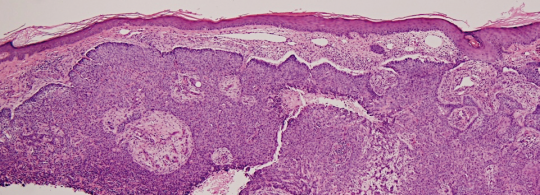

VA94: Right Forehead, Basal Cell Carcinoma, Nodular

- * denote hyporeflective nest structures, arrows indicate bands of collagen compression between adjacent nests